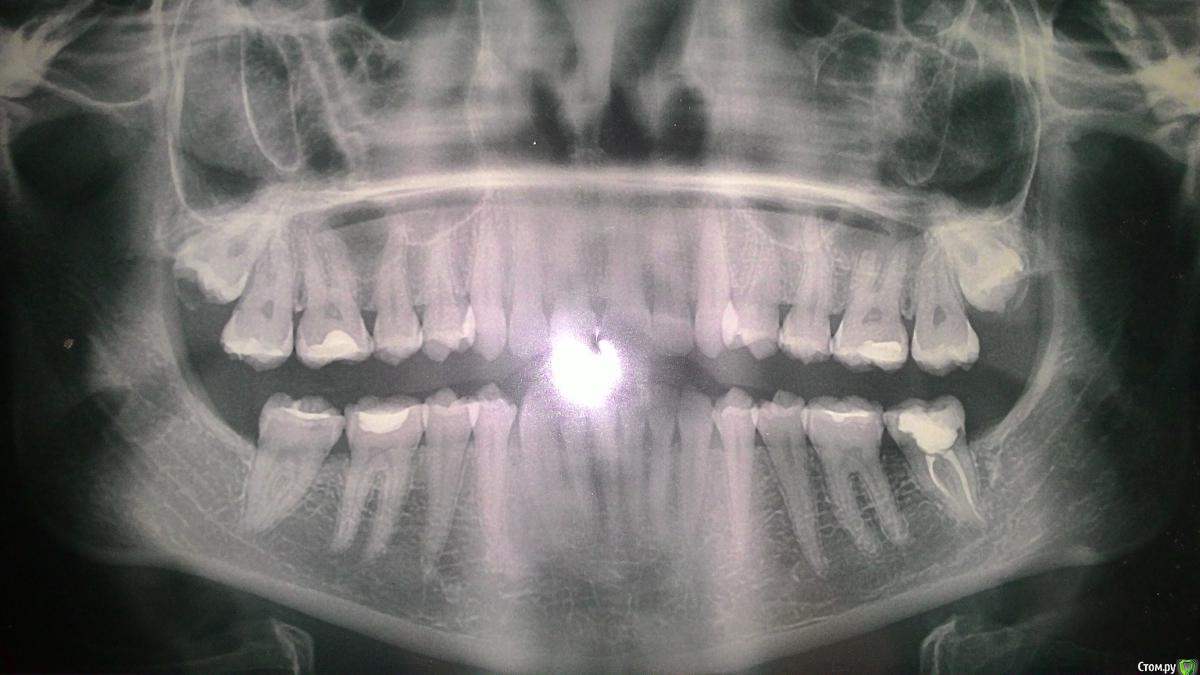

MargaritaM Опубликовано 29 октября, 2016 Поделиться Опубликовано 29 октября, 2016 Здравствуйте! Помогите, пожалуйста, советом, куда идти и что делать. С декабря 2013 года наблюдаюсь на Вучетича у профессора-хирурга (ЧЛХ). Диагноз: ретинированные верхние восьмерки, правая с зубосодержащей кистой. Хирург отказывается удалять, так как не видит хирургических причин удалять. На тему кисты говорит, что ничего страшного, если не растет - с ней можно всю жизнь проходить. Также не хочет удалять, т.к. с высокой вероятностью будет свищ, перфорация в пазуху. Делали ЭОД, хирург указал, что ноющая боль вызвана правой верхней шестеркой. Терапевт говорила, что всё с ней хорошо, но так как года 3 постоянно на нее жаловалась, удалили нерв. Удаление произошло не без приключений: заложили девитпасту на неделю, через 3 дня после заложения пасты адская боль, ее коллега удалила нерв (гноя, запаха не было, нерв не "рвался"), боль держалась, оставили зуб без пломбы на 2 дня, потом закладывали лекарство еще на 2 дня и прописали антибиотики. Боль постепенно стихала, но держалась. Дырку заделали пломбой. Сделали снимок - все каналы заделаны хорошо. После постановки пломбы зуб ныл около 2х недель. До сих пор периодичеки шестерка ныла, особенно когда простужалась или сильно нервничала. Сейчас есть как 4й день ноющая нестихающая боль в области между правой восьмеркой и шестеркой, с усилением ближе к ночи. Первые 3 дня ныла незначительно, сейчас уже сильнее. Есть ощущение, что десна немного припухла, цвет розовый, как у десны около других зубов. Подскажите, пожалуйста, шаг действий и куда еще можно обратиться на тему консультации с дальнейшим лечением/удалением.Пока записалась на прием к другому стоматологу-терапевту на консультацию на 2 ноября. Но сегодня 29 октября, как бы за 4 суток не стало поздно Ссылка на комментарий

kramer Опубликовано 29 октября, 2016 Поделиться Опубликовано 29 октября, 2016 Я бы удалил обе 8ки. Риск перфорации есть всегда, но это управляемо - можно же пластику сделать, ушить. Далее разбираться с 6 зубом. 1 Ссылка на комментарий

kladoffka Опубликовано 30 октября, 2016 Поделиться Опубликовано 30 октября, 2016 Вообще сложностей не увидел в обоих зубах. 2 Ссылка на комментарий

Kazankov.Egor Опубликовано 30 октября, 2016 Поделиться Опубликовано 30 октября, 2016 Кт верхней челюсти сделать нужно, сложности в удалении зубов нет, перфорация верхнечелюстной пазухи - рутинная амбулаторная процедура, решается за 20 минут.Не понятно что будет искать ЛОР. Ссылка на комментарий